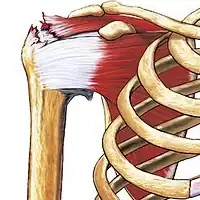

| Some of the muscles of the rotator cuff, with a tear in the supraspinatus muscle | |